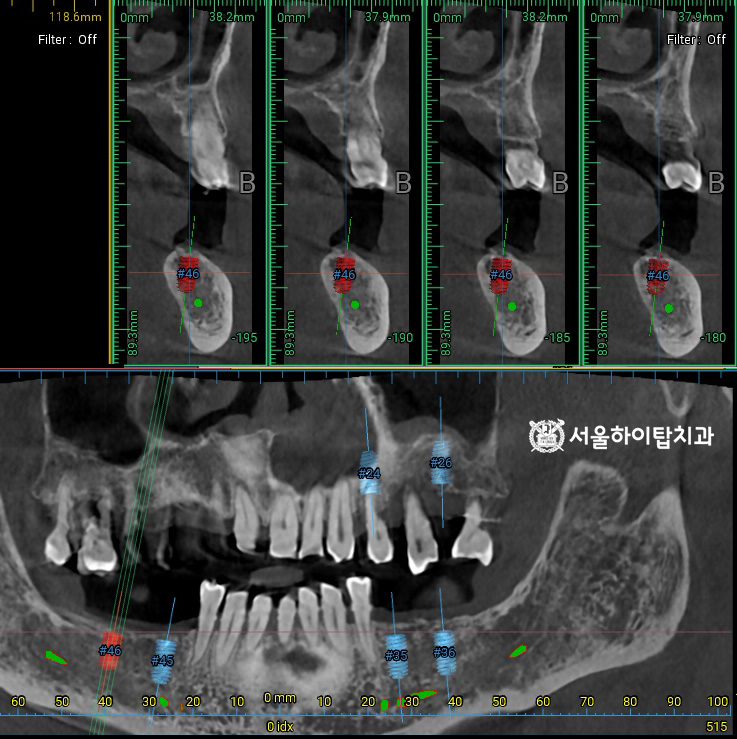

이와 함께, CT 촬영을 통해

픽스처가 식립될 위치를

사전에 시뮬레이션할 수 있습니다.

주안동 치과 에서는 이를 통해

잔존 치조골의 높이, 밀도, 두께,

해부학 구조물 등을 면밀히 분석하고,

시술 과정과 보철 설계를 정확하게

계획할 수 있다고 설명드립니다.